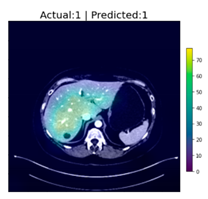

After reaching an accuracy of 95.89%, the training was stopped, and the Grad-CAM method was applied for each of the test images, including those that were falsely classified. The following figure, Figure 6, shows some of the CT images with their associated heat-maps overlaid. In the legends of the figures, “Actual” shows the label for DeepLesion, and “Predicted” shows the output of the CNN classifier.

Figure 6.

CT images with Grad-CAM-generated heat-maps overlaid.